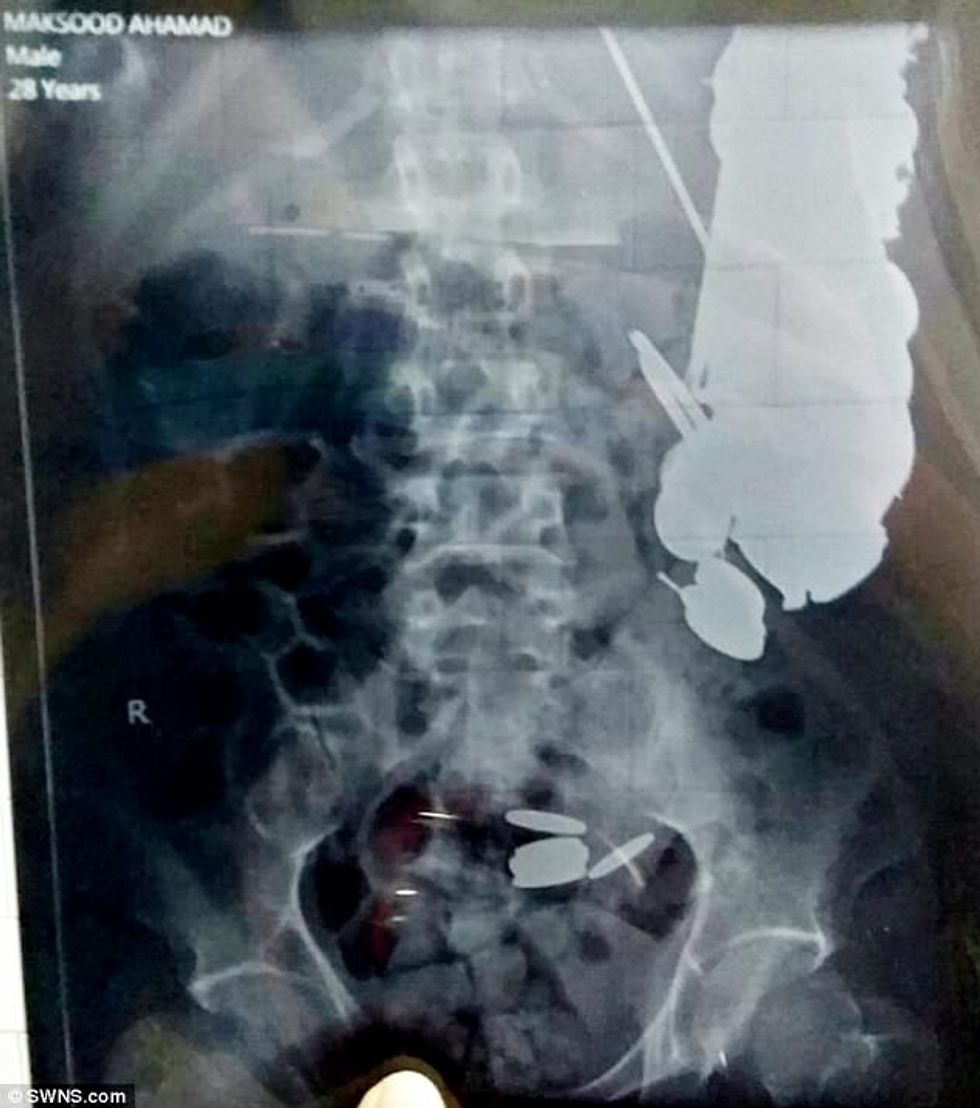

Gjatë operimit, atij i janë larguar 100 gozhda që peshonin një kilogram e gjysmë, si dhe 263 monedha.

Pos këtyre, atij i janë larguar dhjetëra zhiletë për rroje, copëza xhami, si dhe një kapëse metalike, e gjatë 16 centimetra.